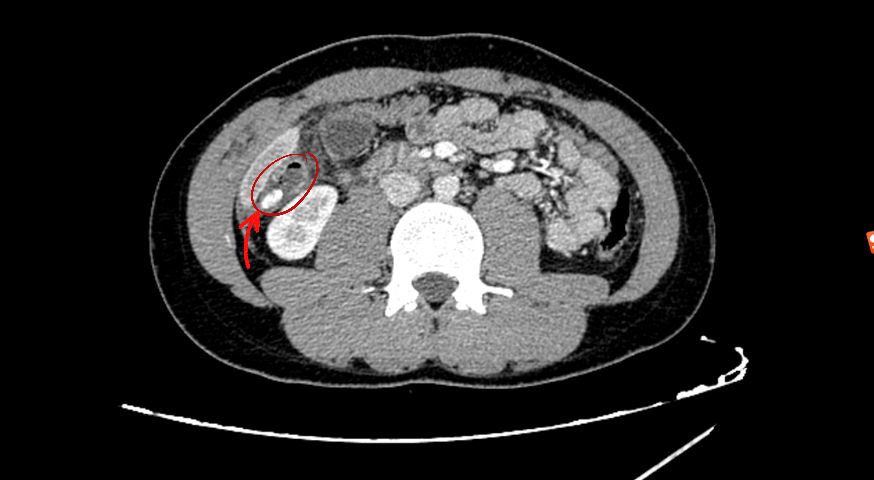

(CT增强显示:结肠肝曲肠管内高密度结节及周围结构改变,类似于“结肠内异物存留”)

▲CT增强显示:异位到结肠肝曲的阑尾